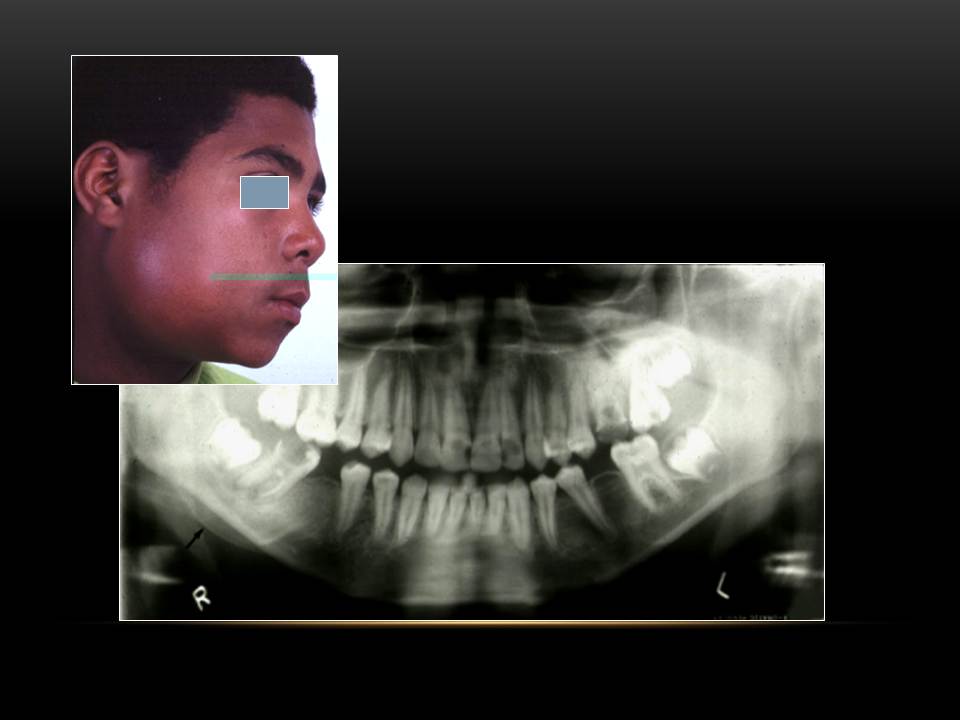

Dentistry Radiographic Image Selection Criteria